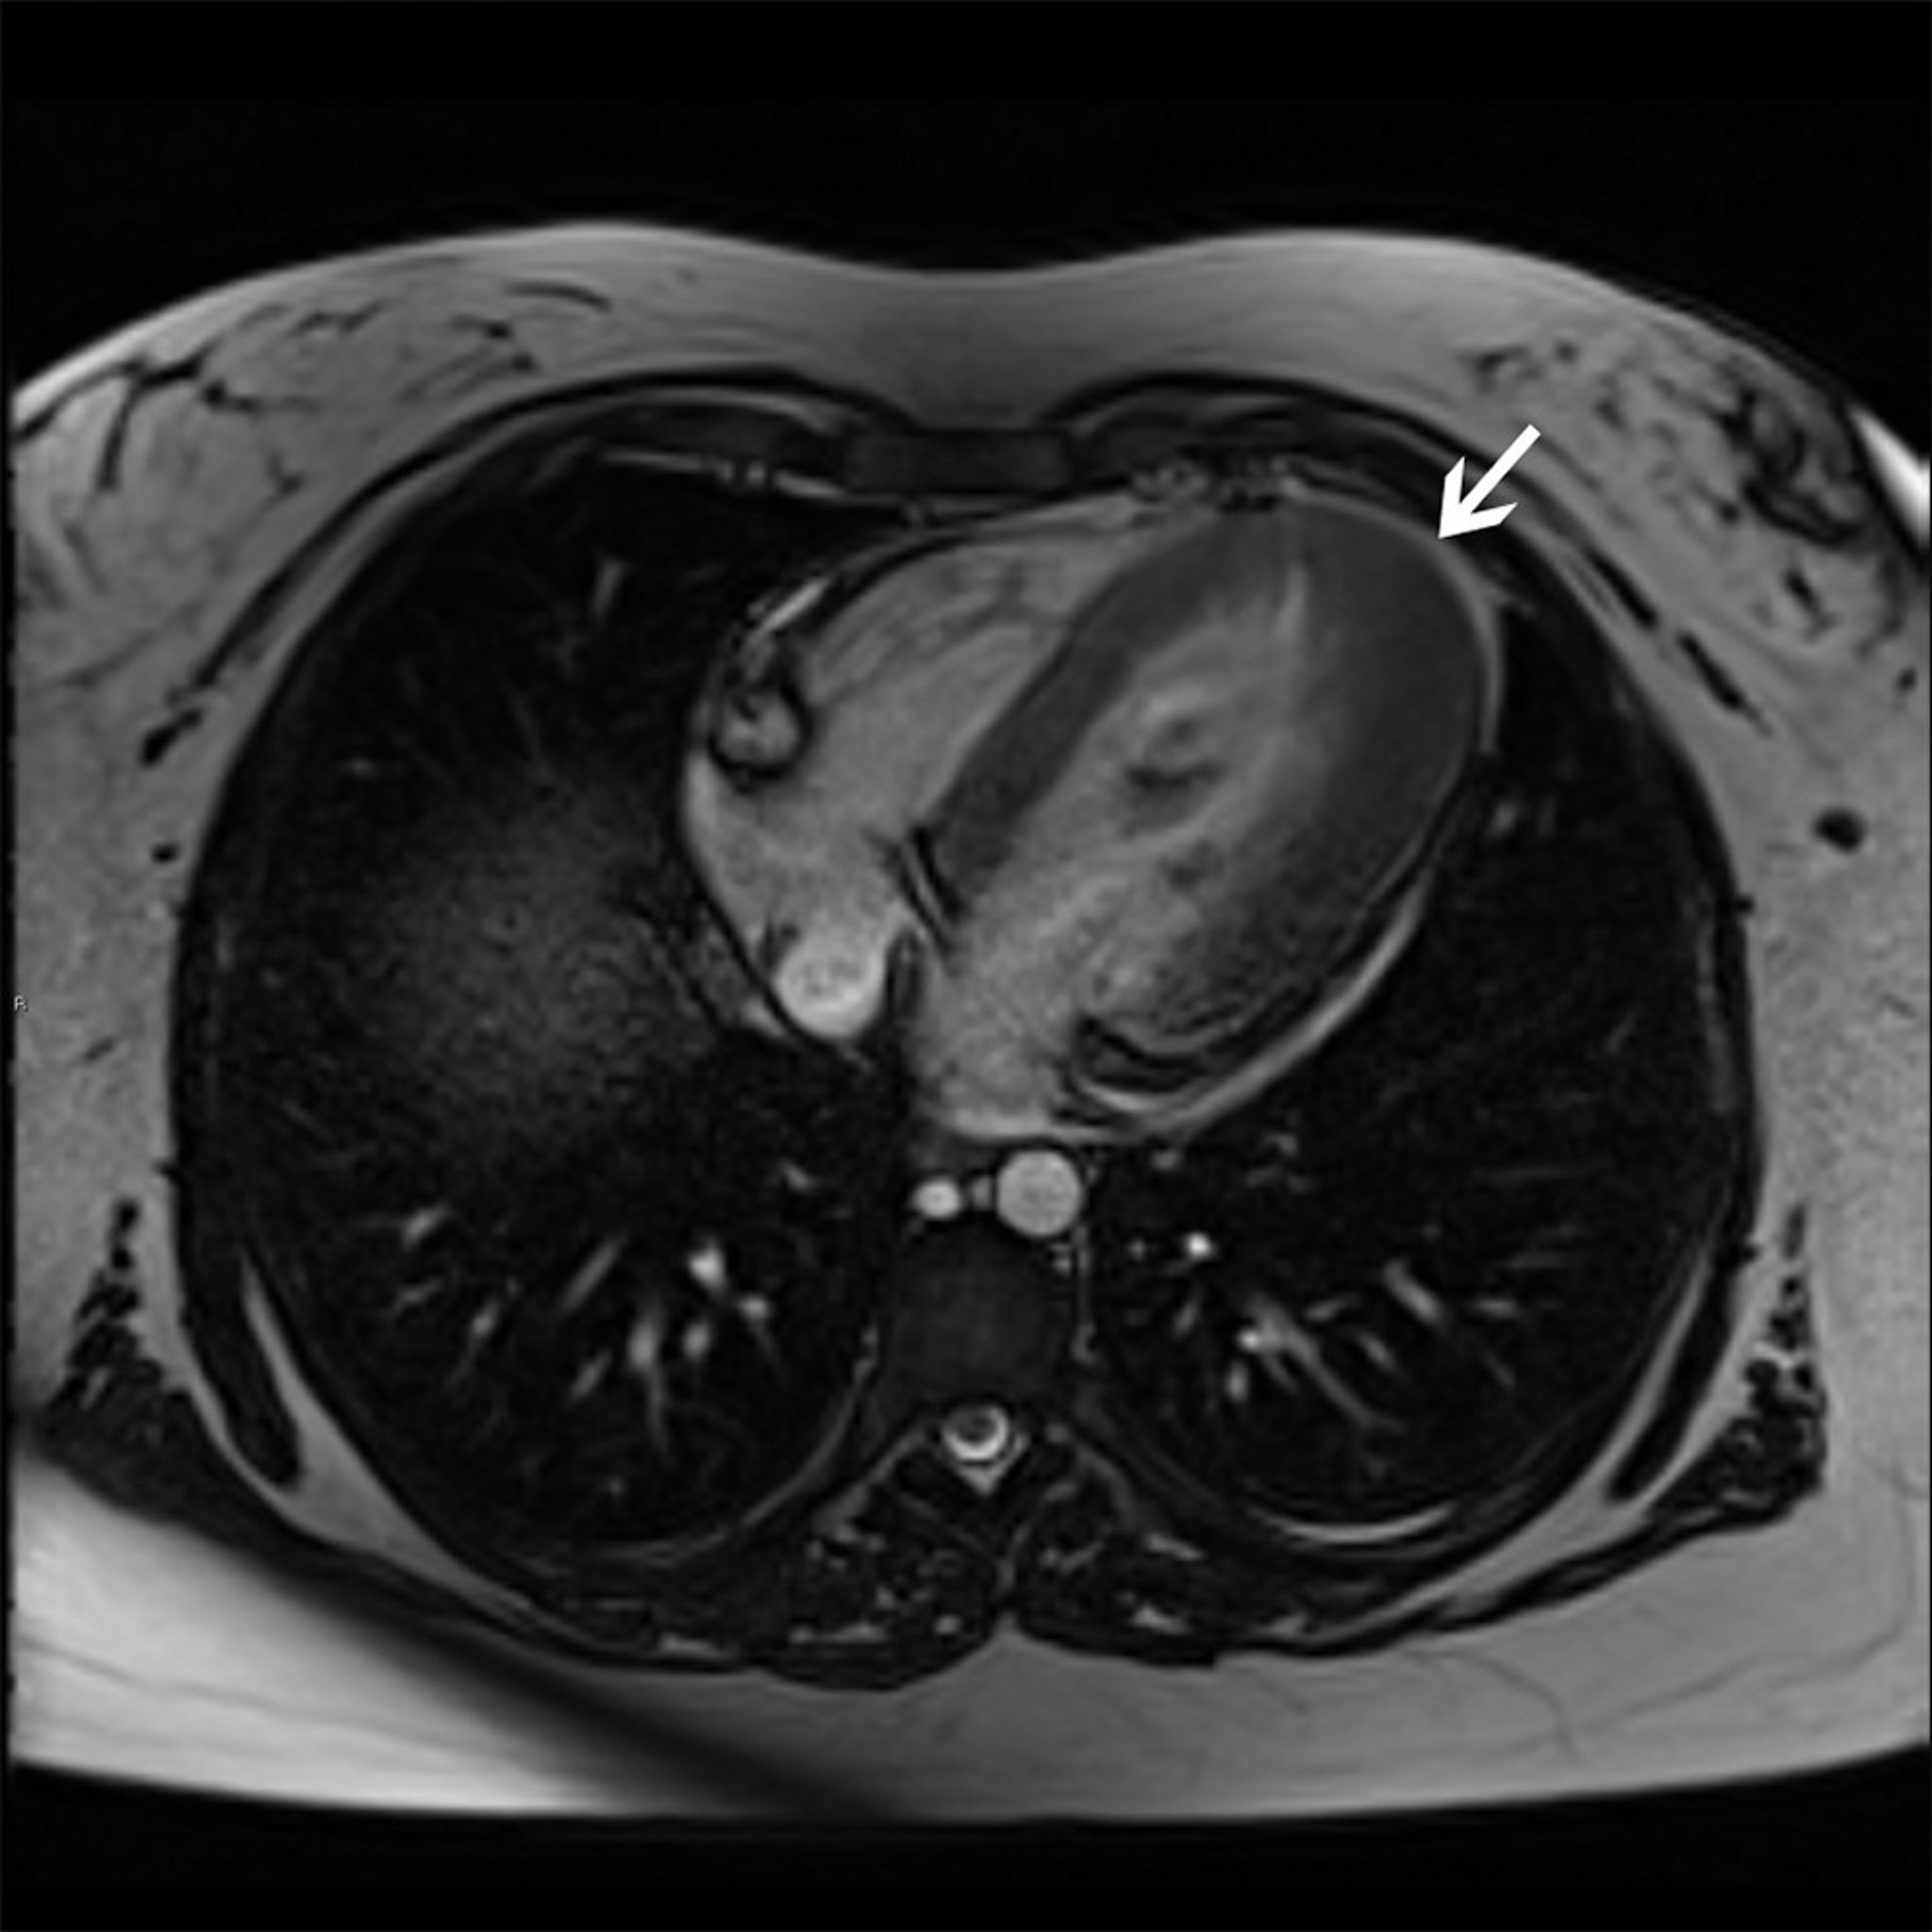

Hypertrophic Cardiomyopathy (Apical Variant)

This cardiac MRI shows apical hypertrophy variant (arrow) of hypertrophic cardiomyopathy.